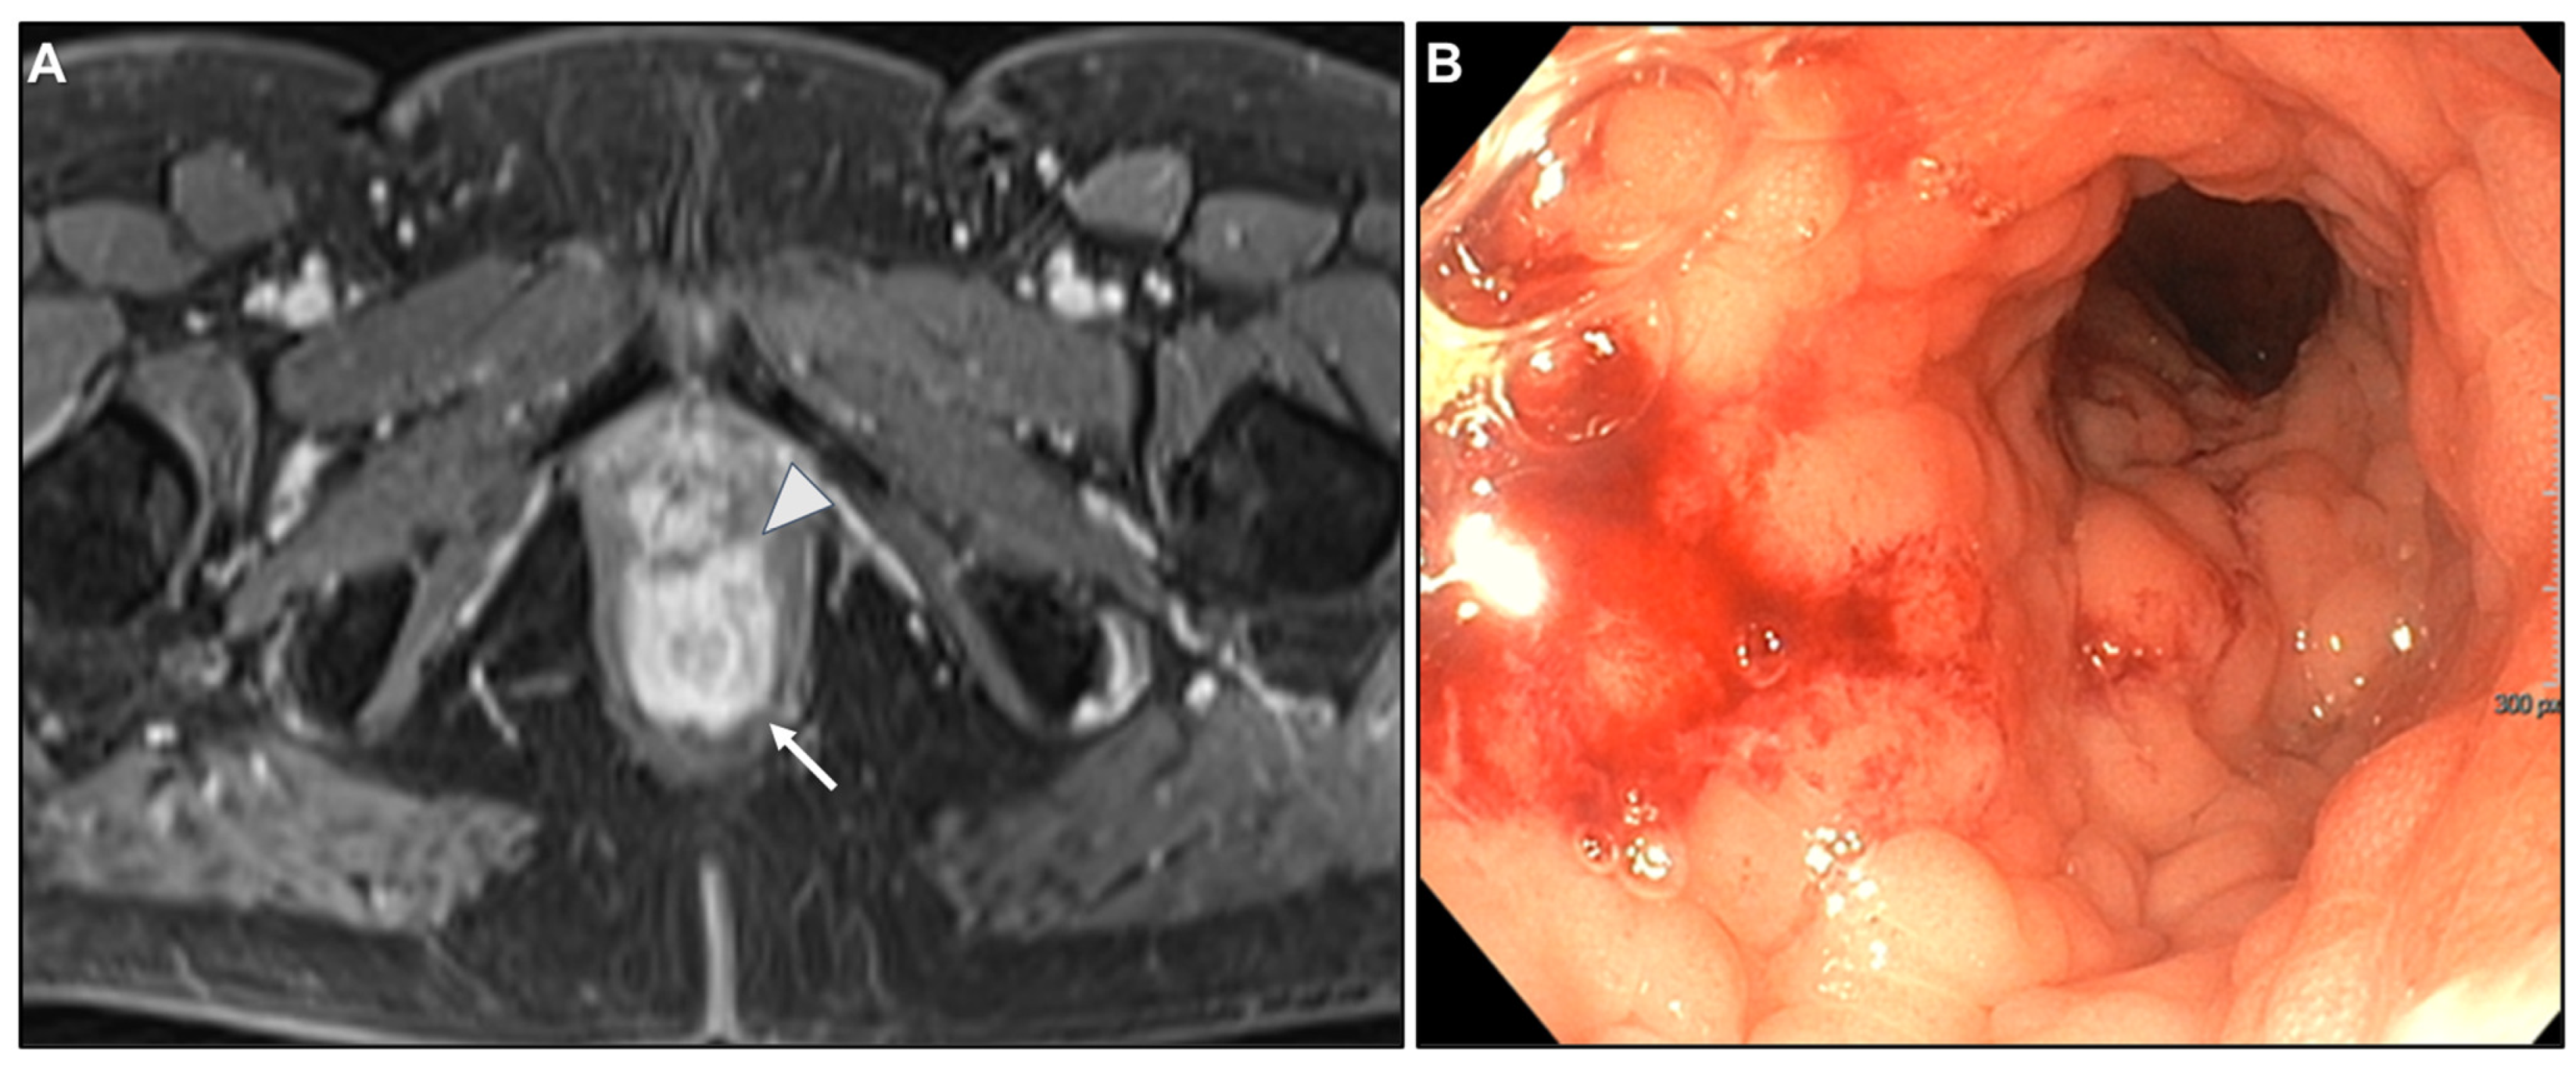

Presacral Fat Tissue and Rectovaginal Septum Infiltration and T2-Weighted Imaging (T2WI) Hypointense Extramural Tumour Component

- Lau, L.C.; Wee, B.; Wang, S.; Thian, Y.L. Metastatic breast cancer to the rectum: A case report with emphasis on MRI features. Medicine 2017, 96, e6739. [Google Scholar] [CrossRef] [PubMed]

- Rudralingam, V.; Dobson, M.J.; Pitt, M.; Stewart, D.J.; Hearn, A.; Susnerwala, S. MR imaging of linitis plastica of the rectum. AJR Am. J. Roentgenol. 2003, 181, 428–430. [Google Scholar] [CrossRef] [PubMed]

- Mazza, S.; Laurenza, C.; Elvo, B.; Tanzi, G.; Ungari, M.; Soro, S.; Verga, M.C.; Drago, A.; Grassia, R. Rectal linitis plastica as the first presentation of metastatic lobular breast cancer: An endoscopic ultrasound diagnosis. Clin. J. Gastroenterol. 2022, 15, 1072–1077. [Google Scholar] [CrossRef] [PubMed]

- Mommersteeg, M.C.; Kies, D.A.; van der Laan, J.; Wonders, J. Linitis plastica of the rectum secondary to prostate carcinoma. BMJ Case Rep. 2022, 15, e248462. [Google Scholar] [CrossRef]